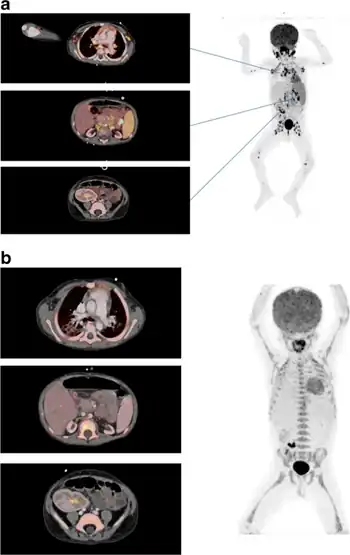

Definitive diagnosis is achieved by biopsying the involved tissue, which will reveal lymphoproliferative neoplasia. Most lesions will show malignant B cells, whereas a minority will show T cell neoplasia. CT imaging may show enlarged lymph nodes or a focal mass. PET scan may be helpful in the evaluation, which may show an increase in metabolic activity (PET avid) lesion, potentially guiding decisions on where to direct biopsies.